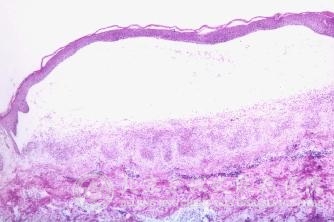

为什么染发过敏皮炎越来越多?染发过敏皮炎是常见的一种皮肤病,染发过敏皮炎经常给人带来无尽的烦恼和痛苦,因此很多人会问这个染发过敏皮炎的问题。染发过敏皮炎给人们的生活工作带来了严重的影响,因此及时了解染为什么染发过敏皮炎越来越多,可以有助于我们及早的预防染发过敏皮炎,以及治疗染发过敏皮炎的皮肤症状。

北京京城皮肤医院指出:随着生活水平的提高,染发的人群越来越多,与染发相关的投诉及到皮肤科看染发过敏的患者不断增加,触发公众对染发 性的关注。染发过敏皮炎发生后应马上就医,如处理得当,则能迅速,反之则拖延病情。治疗应根据皮损炎症状况,选择适当药物。